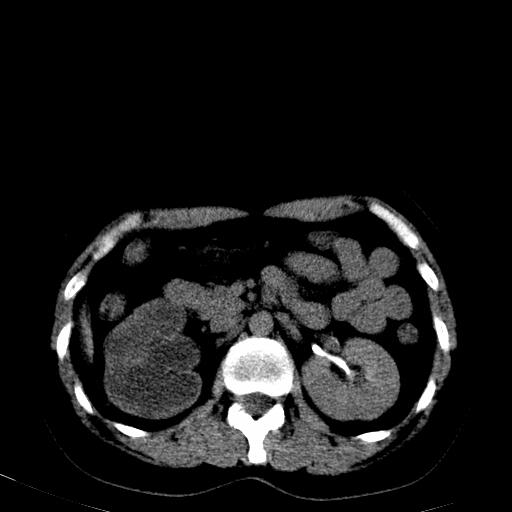

患者体检发现右肾体积增大,怀疑右肾积水

右肾多发囊肿,左肾、左输尿管结石

右肾重度积水,以肾盏积水明显,有分隔,上段输尿管轻度扩张,管壁增厚,考虑肾结核可能,请结合尿检查,胸部拍片排除肺结核。

左肾不像是结石吧,是不是做过造影啊

左肾哪里有结石???

第一个序列应该是延迟图像吧;

结合强化图片看ivp意义不大,建议作逆行造影看一下;

左肾不是结石,是造影后改变.右肾积水,功能仅存.